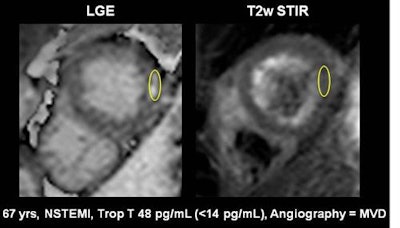

A 67-year-old male patient presenting with non-ST-elevated myocardial infarction (NSTEMI) and moderately elevated troponins, had multivessel disease on invasive angiography. Top image: Late gadolinium enhancement is visible at the lateral wall of the apex in CMR. To distinguish acute from chronic myocardial infarction (MI), the standard approach is to acquire a signal intensity (SI) value from the myocardium, build a ratio with the SI value from a skeletal muscle region of interest, and determine from the previously established cutoff whether the MI is acute or chronic. In this case, the SI was 3.4 (image below), which is above previously established cutoff meaning acute infarction per the standard method. However, CMR TI mapping (below) shows a value of 1020, well under the cutoff of 1037, revealing a chronic infarction requiring no intervention. All images courtesy of Dr. Emver Tahir.Patients with acute and chronic myocardial infarction require different workup and treatment approaches. Treatment isn't generally indicated in chronic myocardial infarction cases, so differentiating the two accurately is important.